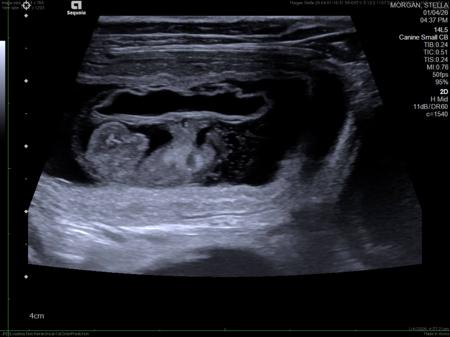

Litter planned in May 2026. Stella (Triscole Aotearoa Artemis) is a daughter of champion whippets in NZ and Banjo (Ingwe Miracle Man) is an Australian Champion. A huge thank you to Swami for allowing Banjo to sire these puppies. Both parents are specialist heart tested. Stella is also eye specialist, DNA and patella luxation tested. The ultrasound shows 5 puppies definitely.